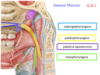

Idenify the indicated internal muscles

Salpingopharyngeus: “from tube to pharynx”

palatopharyngeus: “lateral porion of uvula” “from palate to pharynx”

stylopharyngus: btw gap between superior and middle constrictor; attach to thyroid cartiledge

Identify the indicated internal pharynx muscles